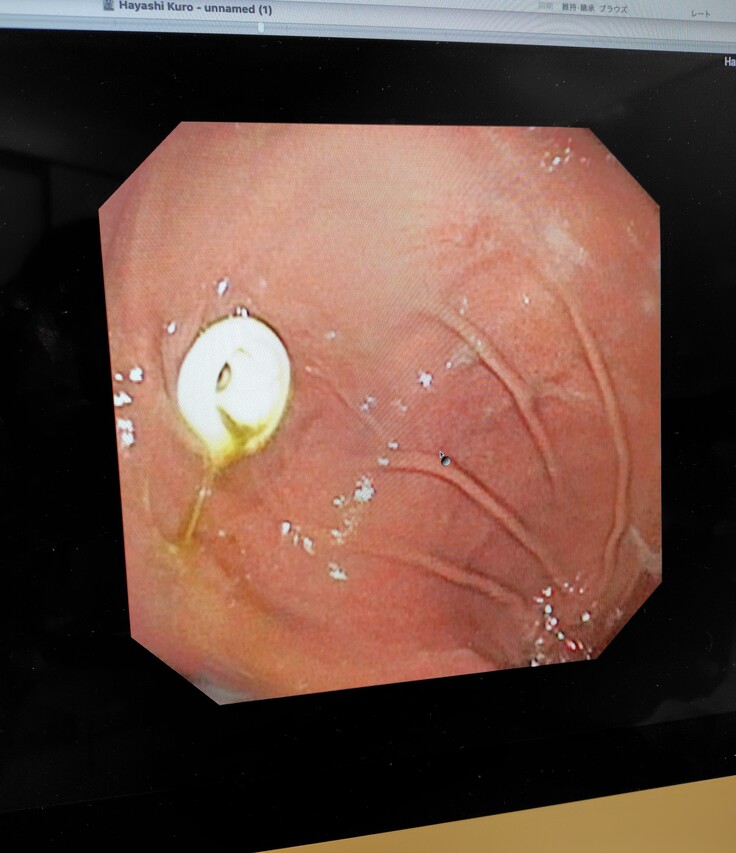

麻酔をし、内視鏡にて再度食道や胃の様子を確認され、食道の手術跡も順調に回復していたようです。胃瘻チューブの穴は医療用ボンドにて埋められそのうち塞がるとの事でした。先生に連れられて出てきてくれましたが、胃瘻チューブも取れてスッキリしてとても気分も良さそうでした😂

食道や胃もキレイな状態です😄本当に手術をしたのかなと思うくらい回復が早いです😄

無事に胃瘻チューブも取れまして、食道もキレイでしたので薬も無く、ご飯もカリカリを混ぜたり少しずつ増やしていき様子をみてくださいとの事で、問題なければ病院での診察は今日で最後となりました。